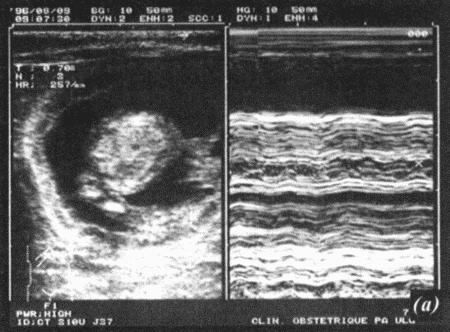

Фиг. 17.2.

Ультрасонографическое изображение (а, b) нормальная беременность (38 дней) в результате естественной вязки; (с) резорбция эмбрионов, индуцированная каберголином в сочетании с простагландином